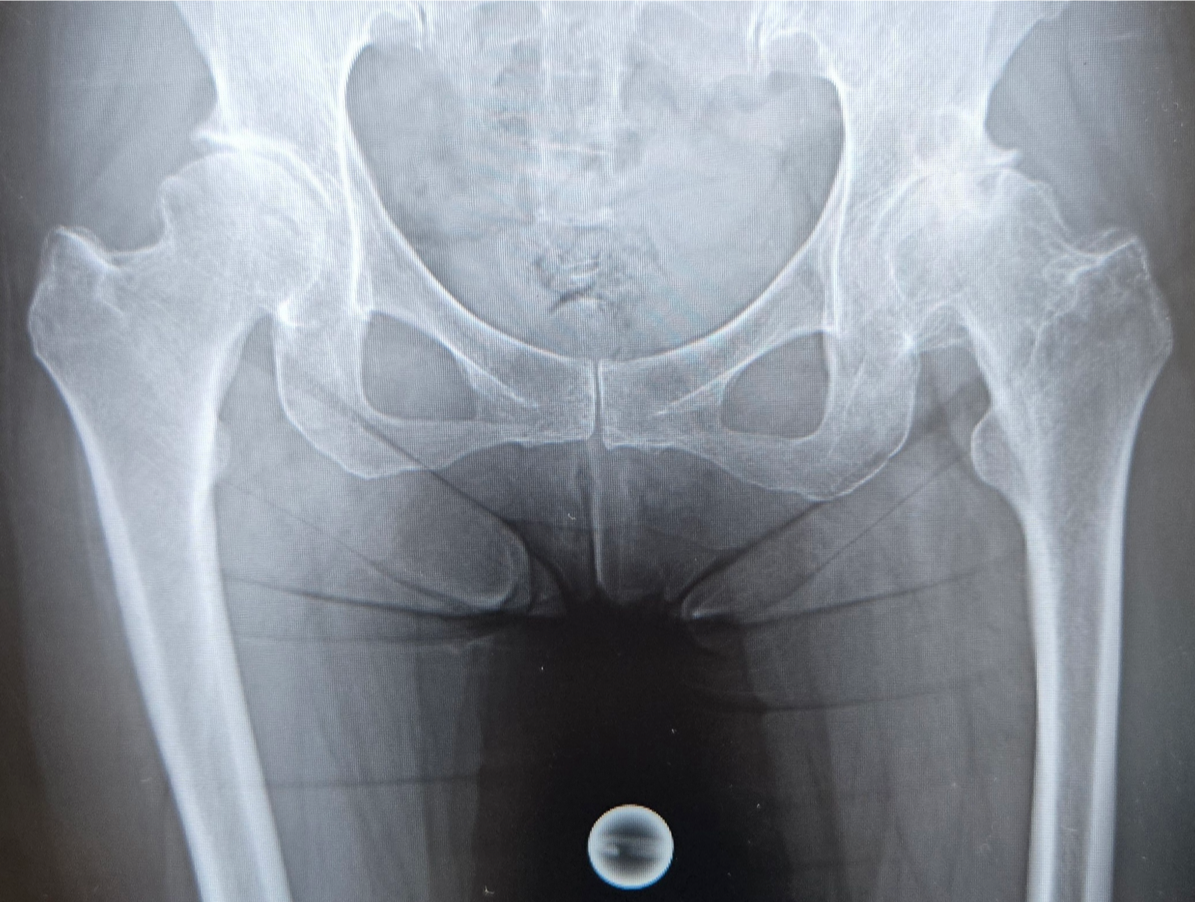

〈手術前のレントゲン〉

当院にて両側の人工股関節全置換術(THA)を施行。アプローチはAMIS(前方最小侵襲手術)で行い、術中に神経ブロックを併用することで、術後の疼痛コントロールを行い、術翌日から離床、リハビリを進めることができました。術後すぐに歩けることに本人も驚いていました。また、術後は一切の肢位の制限も行っていません。